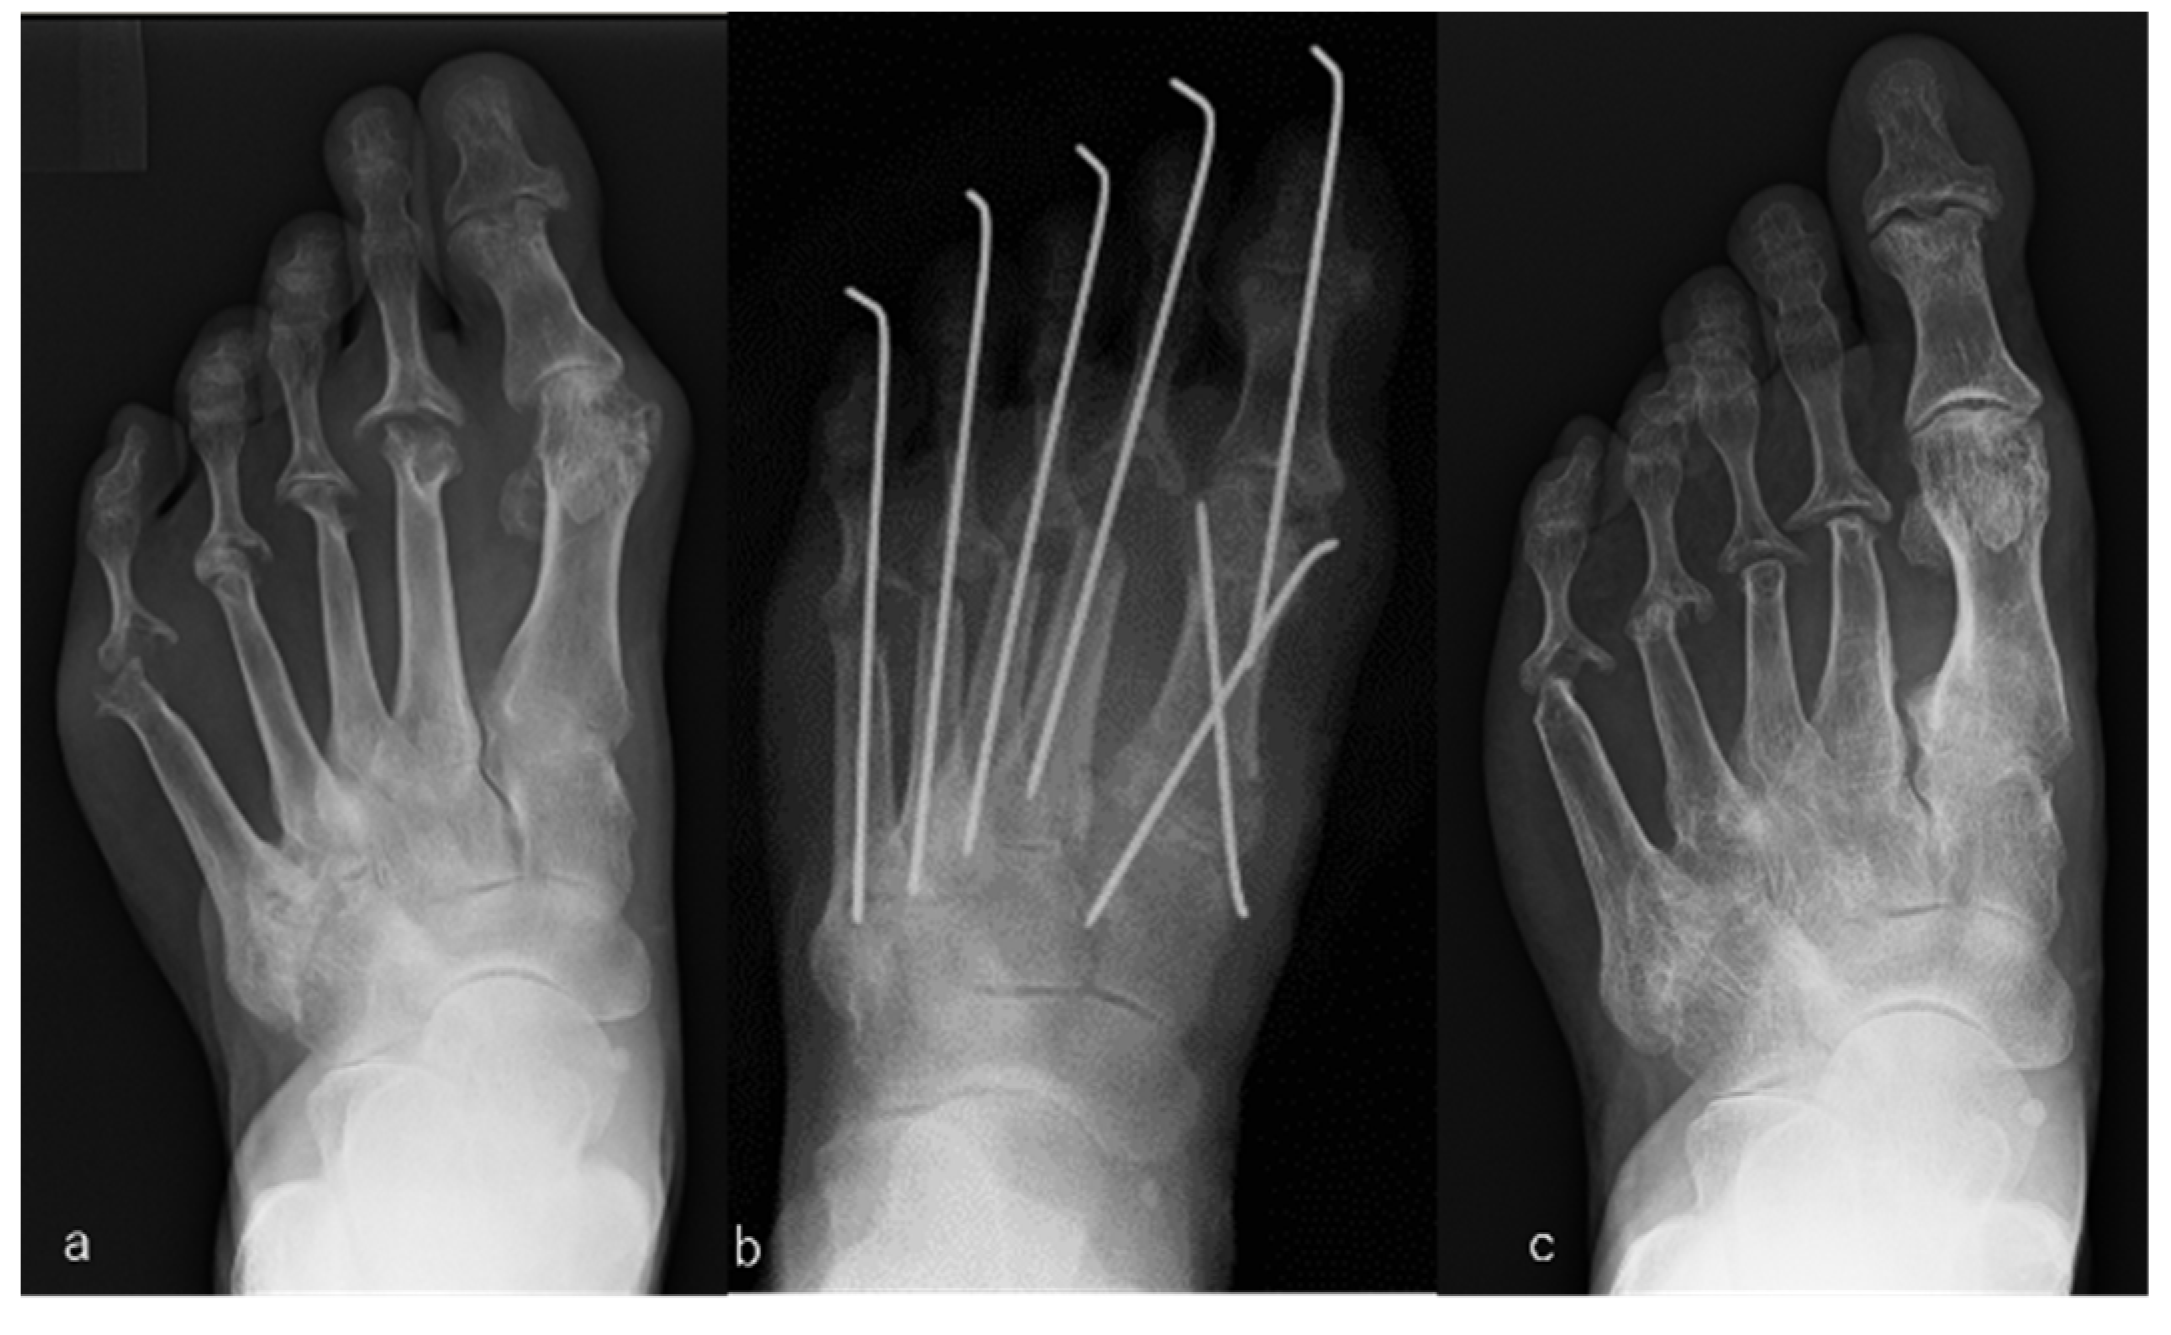

2.4.1. MTP Joint-Preserving Surgery with the Modified Mann Method for the Big Toe and Offset Osteotomy for Lesser Toes

2.4.2. MTP Joint-Preserving Surgery Involving the Modified Mann Method for the Big Toe and Resection Arthroplasty for Lesser Toes

2.4.3. Resection Arthroplasty for the Big and Lesser Toes